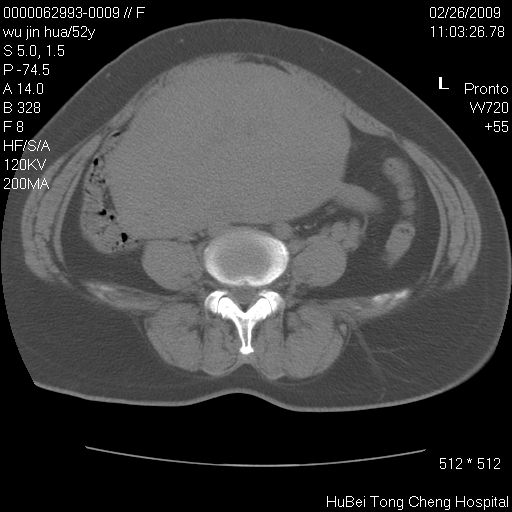

依据平片“腰椎退行性改变”报告,作椎间盘ct扫描时发现:

影像表现:盆腹腔巨大占位,内密度均匀,边界清,未做强化。

来源:考虑来源于腹膜后肿瘤。

性质:以肉瘤可能性大。